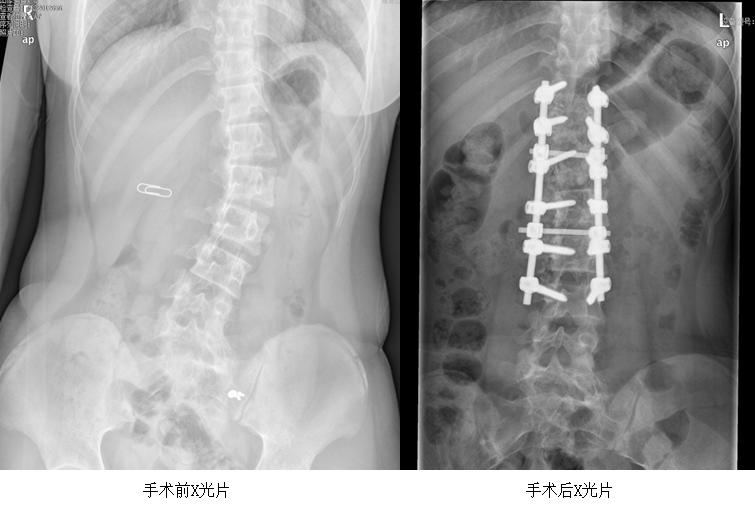

攀鋼總醫(yī)院骨科脊柱外科團(tuán)隊(duì)對小雪的病情進(jìn)行詳細(xì)評估,她的脊柱側(cè)彎角度超過40°,已達(dá)到手術(shù)標(biāo)準(zhǔn),必須進(jìn)行手術(shù)矯正。脊柱側(cè)彎矯正手術(shù)堪稱脊柱手術(shù)的天花板,手術(shù)難度很高。小雪患的是青少年特發(fā)性脊柱側(cè)凸 (Lenke 5CN型),如果矯正不夠,隨著發(fā)育成熟,可能會面臨二次手術(shù);若過度矯正,會導(dǎo)致腰椎活動受限加重。

骨科脊柱外科團(tuán)隊(duì)為確保手術(shù)萬無一失,反復(fù)研究病例,制定了一套縝密的手術(shù)方案。充分的術(shù)前準(zhǔn)備后,在麻醉科的全力配合下,手術(shù)團(tuán)隊(duì)進(jìn)行了經(jīng)后路截骨矯形椎弓根釘棒系統(tǒng)內(nèi)固定、椎板間植骨融合手術(shù),術(shù)中利用自體回收血,術(shù)中喚醒,保障了手術(shù)安全。經(jīng)過5個小時(shí),手術(shù)順利完成。